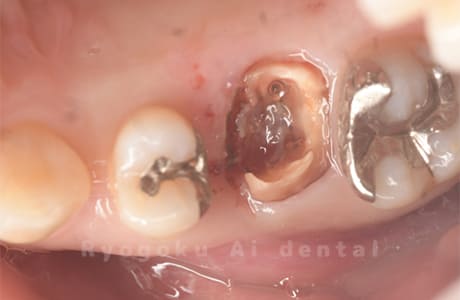

Case10

- 右下6番 重度カリエス

- 右下8を右下6へ移植に自家歯牙移植

- 治療期間

-

- 220,000円

右下の銀歯が外れかかっているとのことでご来院された患者様です。虫歯が大きく、かつ歯が割れており、保存不可能と判断し、親知らずの移植を行いました。